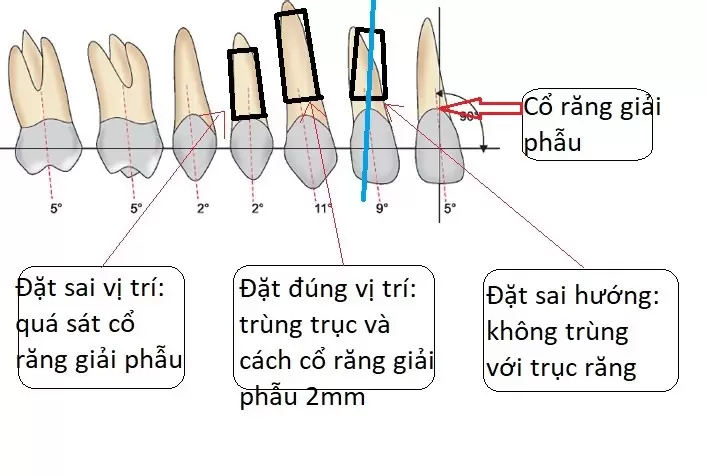

Chân răng của chúng ta, được tiến hóa vị trí dựa trên tác động của lực nhai hàng ngày. Mỗi chân răng đều có hướng trùng khít với hướng truyền lực nhai. Vị trí trụ dọc của chân răng nằm trùng với điểm tác động lực tối đa theo chiều đứng. Chân răng implant được gọi là đặt chính xác khi vị trí. Hướng của nó trùng khít với vị trí tác động lực và phương truyền lực.

Một chân răng đặt đúng vị trí sẽ giúp lực nhai truyền vào đúng trục. Từ đó giúp răng implant ăn nhai tốt hơn, ít bị tiêu xương hơn và sẽ bền vững hơn.

Mặt khác, trong Quy Trình Trồng Răng Implant, giải pháp trồng răng implant cá nhân hóa. Chân implant cần đặt chính xác độ sâu. Để phần trong lợi của trụ phục hình cá nhân hóa có không gian. Từ đó tái thiết lại mô nha chu và tái lập khoảng sinh học quanh răng implant. Khi implant đặt quá nông, Customized Abutment sẽ không thể thiết lập được hàng rào sinh học. Khiến cho răng implant dễ bị tổn thương hơn từ những tác nhân trong khoang miệng.